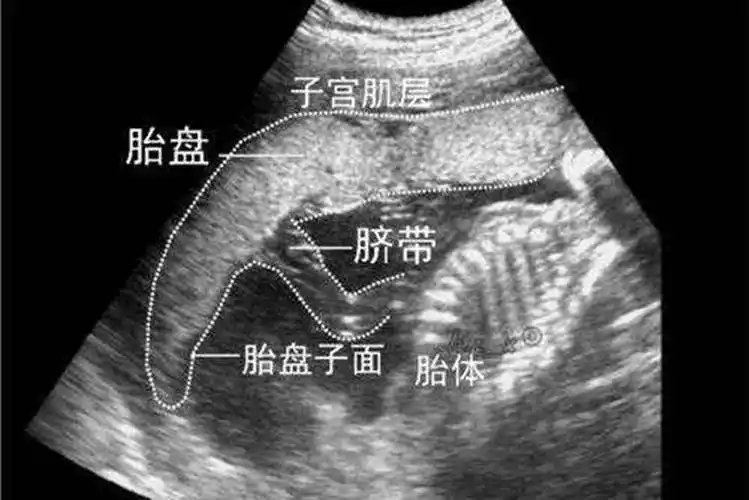

人胎盘详细的特征图片

胎盘是什么样子胎盘形成过程图